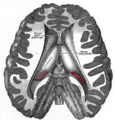

صور إضافية

The pineal body is labeled in these images.